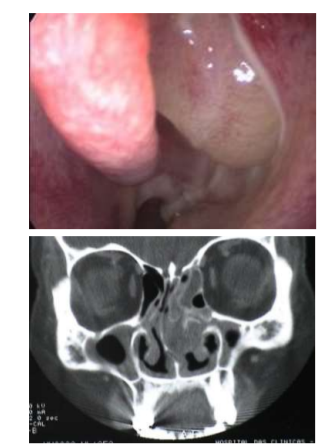

Paciente 38 anos, masculino, vem ao consultório Otorrinolaringológico com queixas de rinosinusites de repetição, obteve melhora acentuada após tratamento para alergia respiratória, porém há 2 meses, após uso de AAS prescrito pelo cardiologista, apresentou exacerbação dos sintomas e, após avaliado clinicamente, foi submetido aos seguintes exames de imagem:

Qual o diagnóstico para este caso: